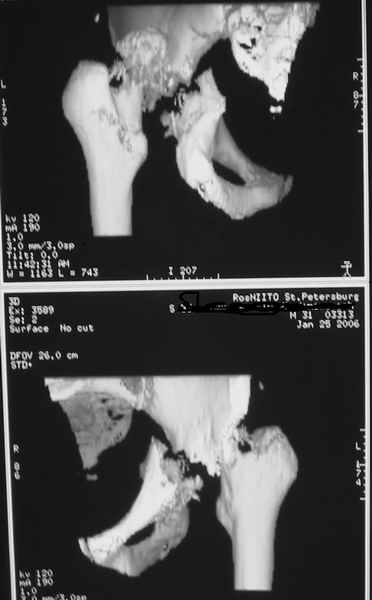

Дорогие коллеги, Поступил пациент, 5 месяцев, как сломался.

Поступил для эндопротезирования, но наши корифеи засомневались, не собрать ли сначала таз. Есть ли смысл собирать аппаратом закрыто?